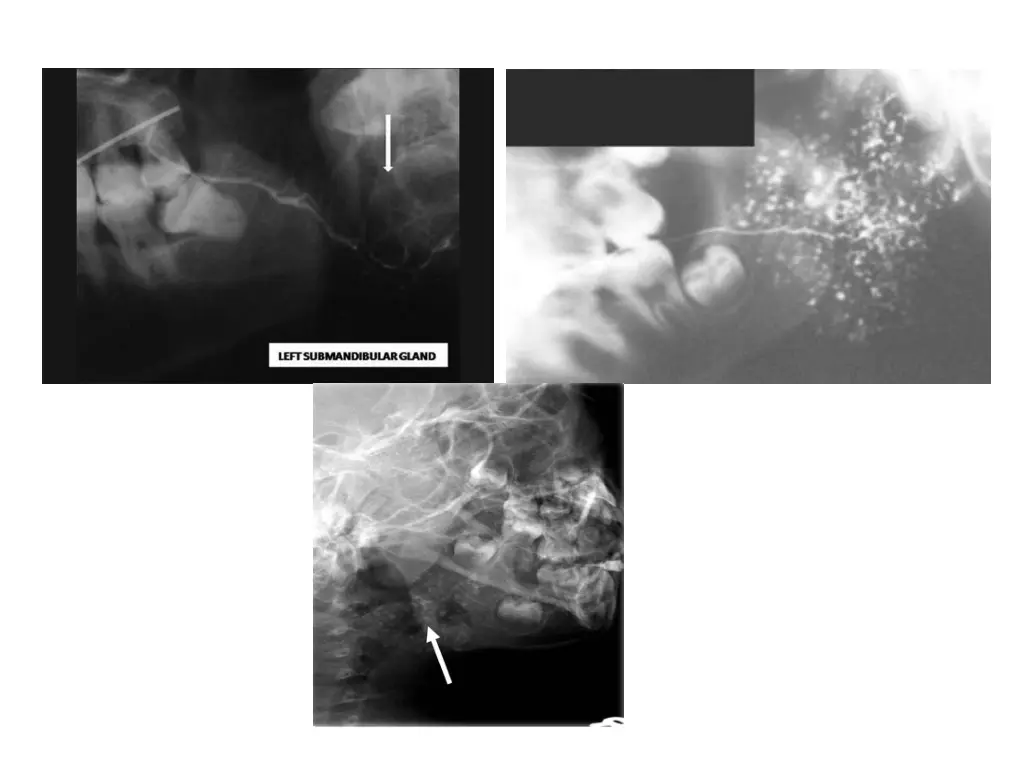

Sialolithiasis Syn: calculus and salivary stone Liths may appear r opaque or r lucent They vary in shape from long cigar shapes to round and oval Homogenous, r opaque internal structure Contrast agent flows around lith, filling the duct proximal to obstruction Ductal system is frequently dilated proximal to obstruction Contrast agent that flows around lith is more r opaque and may obscure small liths R lucent liths appear as ductal filling defects

US is reliable in demonstrating liths More than 90% of liths larger than 2mm appear as echo-dense spots with characteristic acoustic shadow Phleboliths radiolucent center Calcified lymph nodes appear cauliflower shaped

Intraoral r/g Sialoliths in anterior 2/3rdof submandibular duct are imaged with a cross sectional mandibular occlusal projection Posterior part of the duct is demo with posterior oblique view posterior oblique view, here head of pt is tilted back and maximally inclined toward the unaffected side CR is directed parallel with mandible in area of submandibular fossa and into the posterior part of the FOM Liths in anterior part of stensons duct is imaged with intraoral r/g

Extraoral r/g OPG demo stones in posterior duct or demo intraglandular liths in submandibular gland Parotid liths is superimposed over ramus and body in lateral r/g Liths in submandibular gland, lateral projection is modified by opening the mouth, extending the chin, and depressing the tongue with index finger Sialoliths in distal portion of parotid duct PA with puffed cheek